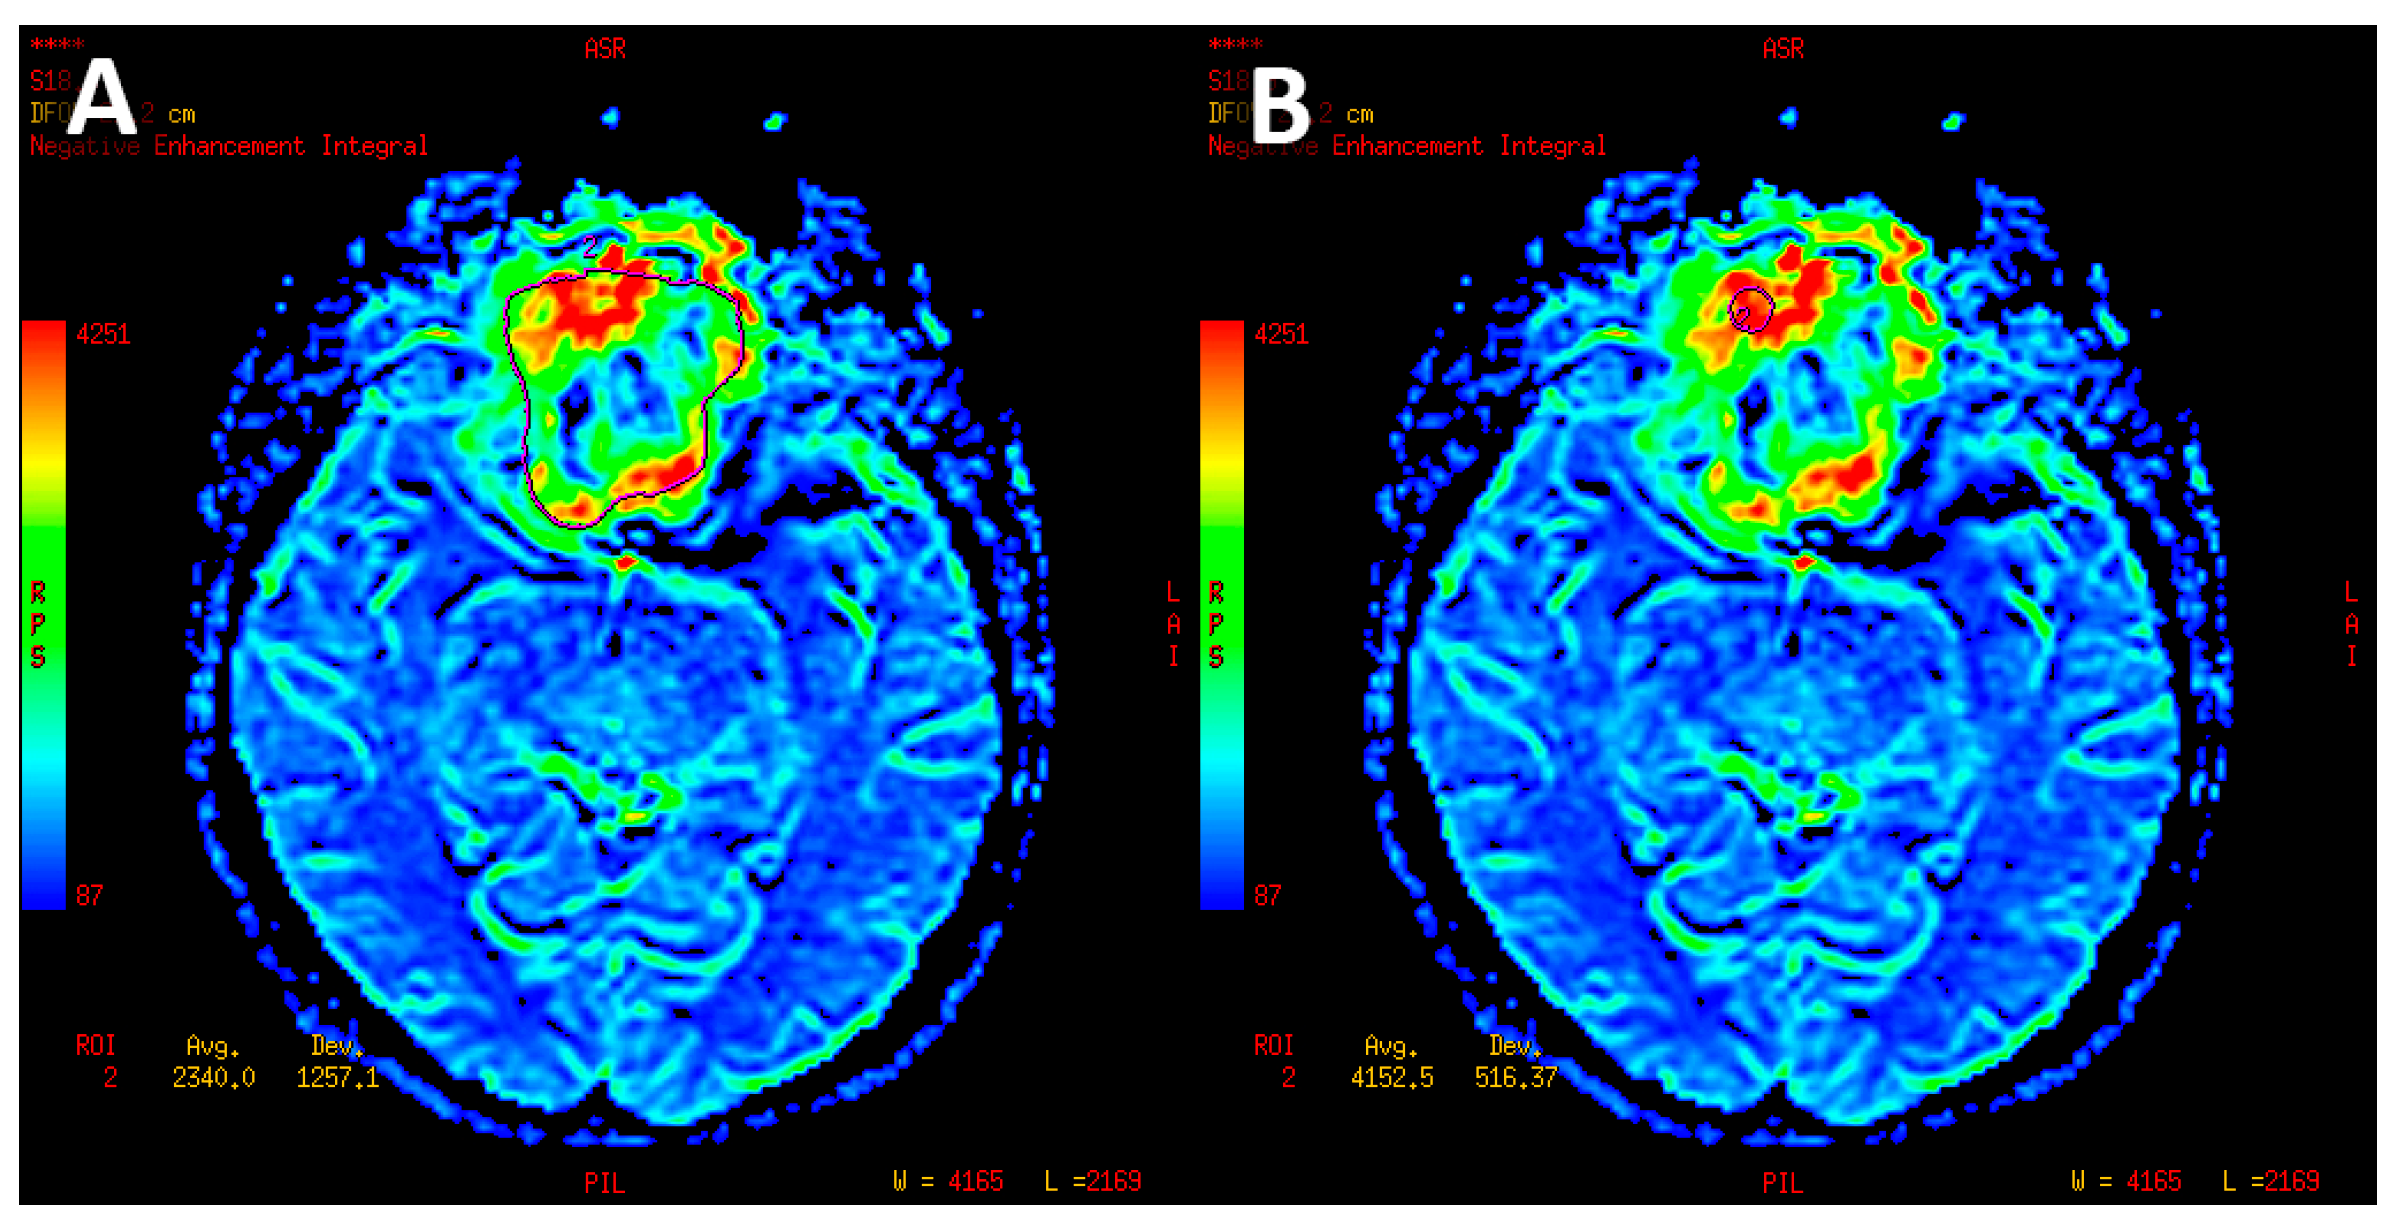

- Mean perfusion parameters for the whole tumor (labeled as rCBV’1)—the arithmetic mean of the perfusion values collected by outlining the tumor with ROIs on each axial slice (Figure 4A).

- Mean of maximum perfusion parameters (labeled as rCBV’2)—the arithmetic mean of the maximum perfusion values collected by outlining the regions with the highest values with circular ROIs (about 30–60 mm2) on each axial slice of the tumor (Figure 4B).

- Maximum perfusion values (labeled as rCBV’3)—the maximum values collected from the whole tumor with a circular ROI (about 30 mm2–60 mm2) (Figure 4B).